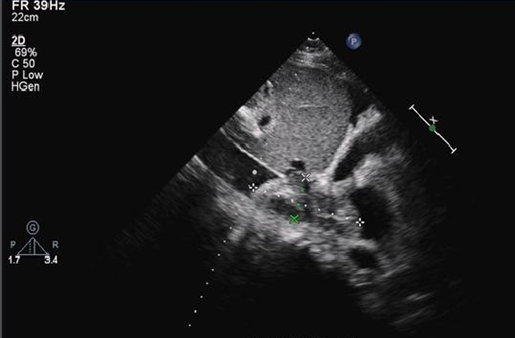

根据临床表现、影像学及肺栓塞临床评分,诊断急性肺血栓栓塞症(中高危组)明确。进一步排查深静脉血栓栓塞的易感因素,其父有肝癌病史,需进一步排查肿瘤因素,同时完善血栓调节组合、抗凝治疗监测组合等相关检查,以了解是否存在先天性抗凝因子缺乏。鉴于患者有溶栓指征,无明显溶栓禁忌证,将溶栓风险告知患者及家属,其理解并同意溶栓治疗,于2017年6月15日16:00予阿替普酶50 mg静脉持续泵入2 h溶栓治疗,溶栓时及溶栓后密切监测凝血功能变化。此外,结合患者胸部CT提示肺部有渗出,血白细胞升高,有发热、明显咳嗽、咳痰症状,考虑社区获得性肺炎(非重症),有使用抗生素指征,结合社区感染相关病原体,予左氧氟沙星0.5 g ivdrip qd经验性抗感染治疗。经上述治疗,患者仍有气促,间断咳嗽,咳少量血丝痰,2017年6月17日腹部彩超提示:①双侧少量胸腔积液;②肝静脉,汇入下腔静脉低回声,血栓形成可能;③肝、胆、脾、胰、肾、输尿管、膀胱、前列腺均未见异常。复查其凝血功能未达标,加用华法林抗凝治疗,初始剂量3 mg po qn,考虑药物需3~5 d才能达到稳定的血药浓度,为达到快速抗凝目的,使INR达到2~3,继续予低分子肝素0.8 ml H q12h重叠抗凝。同时为了解华法林量效关系,予完善CYP2C9和VK0RC1检查,通过基因多态性检测,有助于指导华法林初始剂量的选择。抗凝治疗期间多次复查凝血功能,根据结果调整抗凝药物剂量。溶栓后5 d,患者仍诉气促,呕吐频繁,反复低热,热峰不超过38℃,复查床边胸部X线片提示右侧大量胸腔积液(图2),行超声引导下胸腔穿刺置管引流术;查肝功能示转氨酶升高,予护肝治疗;加强抗感染(亚胺培南西司他丁1.0 g ivdrip q8h)。患者症状无明显好转。2017年6月20日开始频繁诉恶心呕吐,吐出胃内容物,发热,气促,活动后加重,咳嗽,咳血丝痰,无明显胸痛或胸闷不适,右侧胸腔引流管引流出血性液体。查体:神清,双上肺及左下肺呼吸音清,右下肺呼吸音明显减弱,未闻及干/湿啰音,心率111次/min,各瓣膜区未闻及病理性杂音。腹部平坦,肝右肋缘下5 cm可触及,质软,无触痛。复查出、凝血常规示:D-二聚体25.07 mg/L FEU,INR 3.19,APTT 49.7 s;ESR 56 mm/h;胸腔积液检查结果提示渗出液。取胸腔积液标本找肿瘤细胞。复查心脏彩超:下腔静脉肝后段至右心房实性回声,考虑血栓形成,估测肺动脉压28 mmHg(图3)。考虑恶心呕吐与肝静脉血栓形成、肝淤血致肝功能异常相关,停用可能导致肝损害的药物,继续抗凝,加强护肝、退黄、平喘治疗及营养支持。经上述治疗,患者气促情况有好转,但肝功能损害加重,肝酶、胆红素及血氨水平进行性升高,凝血功能明显异常,ALT 1819 U/L,AST 6345 U/L,LDH 5860 U/L,TBIL 70.8 μmol/L,DBIL 27.6 μmol/L,IBIL 43.2 μmol/L,维持护肝、降血氨治疗,及时纠正非预期凝血功能障碍,复查胸+上腹+下腹CTA平扫+增强+三维,查风湿组合Ⅰ+Ⅱ,自身免疫性肝病组合,抗磷脂综合征组合等相关检查,帮助明确肺血栓情况,查找肝功能进行性异常的原因,风湿免疫相关检查结果无异常。2017年6月22日行CTA示:①肺动脉主干,左、右肺动脉干,左上、下肺动脉及其分支,右下肺动脉主干及外基底段近段肺动脉栓塞,左下肺动脉栓塞较前范围稍扩大,右下肺动脉病变范围较前稍减轻;下腔静脉近右心房至肝段上部、下腔静脉肾静脉水平—双侧髂总静脉—双侧髂外静脉及肝左、中、右静脉管腔多发血栓形成,较前进展。②肺部炎症、胸腔积液。③心包积液较前稍增多,腹腔、盆腔少量积液(图4)。注:A:右心房血栓;B:下腔静脉延续到右心房处血栓,肝静脉未显影;C:CTA示下腔静脉近右心房端、肝静脉多发血栓形成;D:CTA另一层面示下腔静脉血栓,肝内静脉未显影,考虑栓塞;E、F:复查胸部CTA示肺动脉主干栓塞6月22日夜间患者出现谵妄、躁动不安,不能正确应答,查血氨升至191 mmol/L(图5)。考虑患者多部位静脉血栓形成,肝静脉栓塞,肝脏淤血明显,已并发肝性脑病,有急性肝衰竭可能,予乳果糖口服溶液灌肠,门冬氨酸鸟氨酸降血氨治疗,患者解出大便后症状稍好转,密切观察肝功能变化情况。请院内多学科会诊,多学科意见考虑患者目前存在多部位静脉血栓,急性肝损伤,凝血功能严重异常,手术风险极大,不建议行手术取栓治疗,建议继续内科药物治疗,可考虑行二次系统溶栓。与患者及家属沟通病情并取得知情同意后,2017年6月25日行第二次溶栓,予阿替普酶50 mg静脉持续泵入2 h,同时密切观察全身出血情况,预防出血,继续对症支持治疗。患者意识障碍加重,尿少,出现肝肾综合征,凝血功能异常。床边腹部超声:①右肝静脉血栓形成、闭塞,中肝静脉第二肝门处血栓形成,血流通畅,双向血流;②下腔静脉血栓形成,彩色多普勒血流成像(CDFI)探查不佳;③左肝静脉双向血流;④肝动脉、门静脉血流通畅。当天患者意识障碍进一步加重,昏迷状,呼吸衰竭,行气管插管接呼吸机辅助通气,气道内吸出血性分泌物,多次复查结果示肝功能及凝血功能严重异常,低纤维蛋白原血症,考虑存在肝静脉、下腔静脉血栓相关的布加综合征。请血液科会诊,考虑低纤维蛋白原血症系由肝损、溶栓药物、DIC消耗等多因素引起,建议完善凝血因子监测,根据结果及INR补充新鲜冰冻血浆、凝血酶原复合物、维生素K1等。患者因少尿,行床边连续性肾脏替代治疗(CRRT),体外肝素化抗凝,但因滤器及管路凝血而提前结束治疗。请感染科会诊,建议继续予护肝、降酶、退黄治疗,补充血浆及白蛋白,加强肺部及腹部抗感染治疗。请血管外科会诊协助处理肝静脉血栓,血管外科建议考虑下腔静脉、肝静脉机械取栓或置管溶栓,辅以全身肝素化抗凝,以改善肝脏血流,但因手术风险极高,家属不愿行取栓/溶栓术。虽给予积极药物治疗,患者肝功能改善情况不理想,凝血功能差,反复输注血制品情况下出现顽固性低纤维蛋白原血症,合并全身散在部位出血,预后差,2017年6月30日家属办理自动出院手续。| 该患者入院时无明显血流动力学不稳表现,影像学显示双肺动脉栓塞较严重,存在肺动脉骑跨,发病早期即发现肝静脉、下腔静脉多发血栓形成,入院后1周内出现肝衰竭,病程进展迅速。针对该患者的治疗难点有哪些?回顾这一病例,是否有更有效的方法进行治疗? |